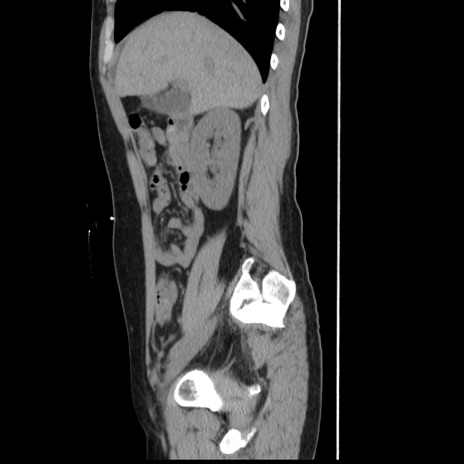

横断像

冠状断像

【症例】 50歳代女性

【主訴】 腹痛

【現病歴】前日生レバーを食べた。今朝に排便あり。 昼前に突然発症の腹痛を生じ、当院救急外来を受診した。

【既往歴】 子宮筋腫にてで子宮全摘後

【身体所見】 意識清明、腹部:平坦、軟、下腹部やや左を中心に圧痛・反跳痛あり、筋性防御あり

【データ】WBC 7800、CRP 0.07